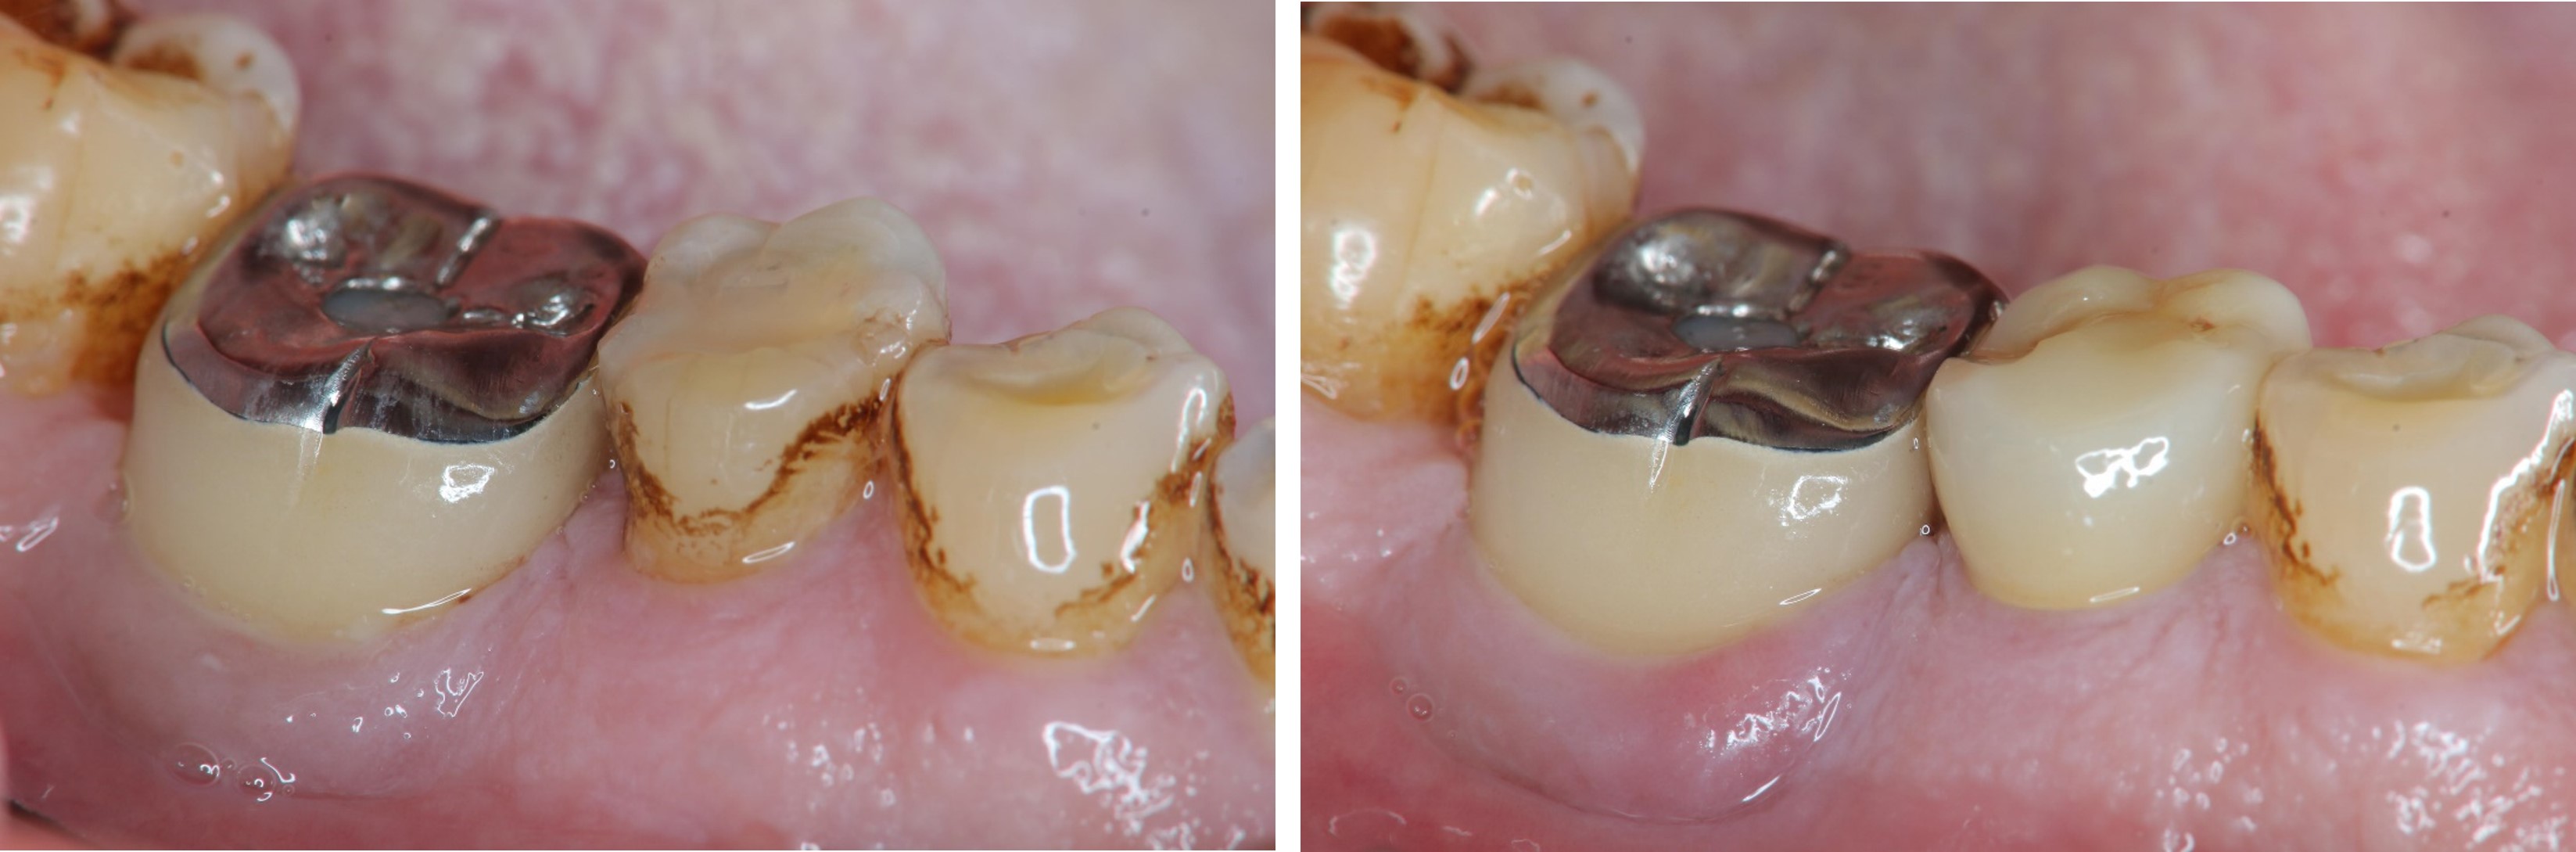

牙周-膺復合併治療-牙齦下蛀牙-#37

根管治療

牙髓/牙周/膺復合併症